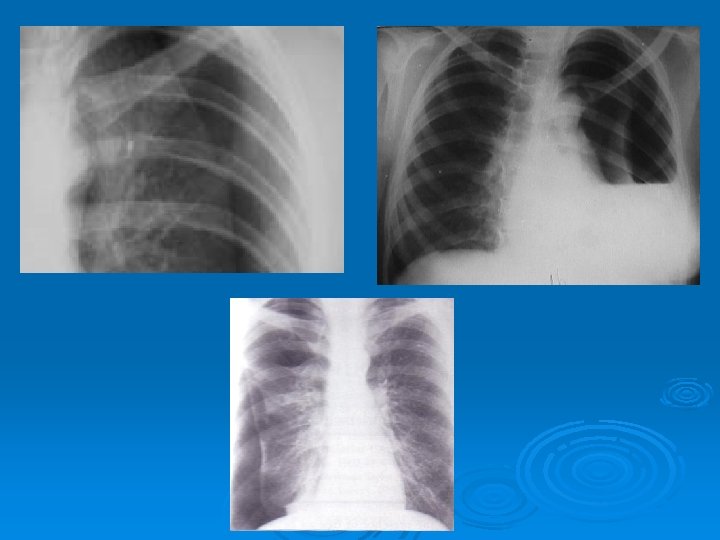

Radiology The fluid initially accumulates in the more dependent recesses of the thoracic cavity forming a Damoiseau Line Ø 200 -300 ml of pleural effusion can be detected on standard chest radiograph as blunting of the costophrenic angle Ø

Ø Massive pleural fluid often shifts the mediastinum to the opposite side Ø Unusual localized pleural effusions can be seen due to the localized obliteration of the pleural space often by inflammatory conditions (adherence)

Ø Smaller amounts of pleural fluid can be detected on lateral decubitus radiography as the free intrapleural fluid moves from top of the diaphragm to the dependent chest wall Pleural effusion in a lateral decubitus radiograph